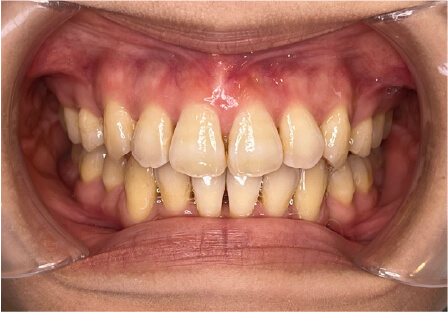

叢生の症例

10歳

/

女性

相談内容

スペース不足

カウンセリング・診断結果

myoからの移行。スペース不足のためインビザライン開始。

治療内容・方法

全額アライナー矯正

術後の経過・現在の様子

クリアライナー使用

治療のリスク

痛み・歯根吸収・歯肉退縮・虫歯・後戻り

費用・治療期間

(インビザのみ)385,000円、1年2ヶ月 + myo3年4ヶ月

トレーニングなど